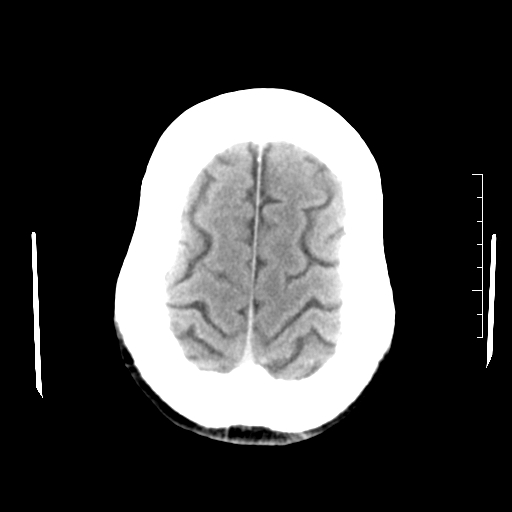

以下是引用随光逐影在2010-7-22 20:48:00的发言:[br]1)考虑左侧颞枕叶及左侧小脑脑梗塞。2)左侧半卵圆中心多发性腔隙性脑梗塞。[br]建议:必要时行mri检查。

以下是引用linyiming在2010-7-23 1:17:00的发言:[br])考虑左侧颞枕叶及左侧小脑脑梗塞。2)左侧半卵圆中心多发性腔隙性脑梗塞。[br]建议:必要时行mri检查。 [br]